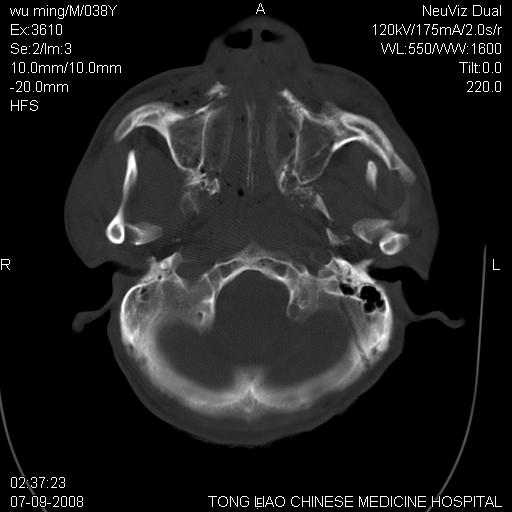

标题: CT14544:患者5楼坠下15分钟后CT扫描,2小时后死亡,请战友指 [打印本页]

标题: CT14544:患者5楼坠下15分钟后CT扫描,2小时后死亡,请战友指

颅底多发骨折.上颌骨多发骨折

右侧眼眶,上颌骨,鼻骨、上颌窦等很多

考虑:面骨、颅底骨多发骨折,颅内高压(脑肿胀)。

1)颅底骨及颌面骨多发性骨折。2)副鼻窦及双侧鼻腔积血。

颅底骨折,窦腔内积血。考虑死亡原因为脑水肿压迫脑干或因大量失血死亡。

颅底、上颌骨,双侧颧骨多发骨折。死因或许与此无关,是否有腹部脏器损伤有关